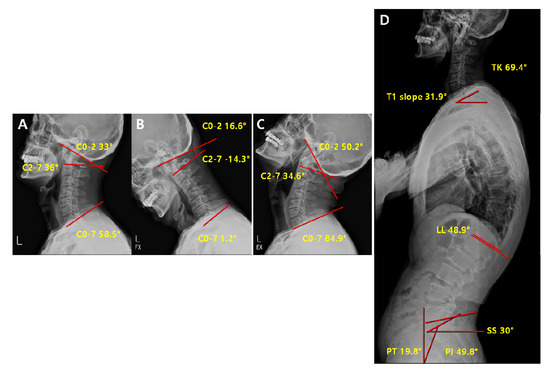

| Parameters | Definition |

|---|---|

| C2-7 Cobb angle | The intersection angle between the line perpendicular to the line parallel to the C2 lower endplate and the line perpendicular to the line parallel to the C7 lower endplate |

| C0-2 Cobb angle | The occipito-cervical angle, which is the intersection angle between the McGregor line and the line parallel to the C2 lower endplate and is used to evaluate the curvature of the upper cervical spine |

| C0-7 Cobb angle | The intersection angle between the McGregor line and the line parallel to the C7 lower endplate |

| C0-2/C0-7 | The value of C0-2 Cobb angle divided by C0-7 Cobb angle |

| C2-7/C0-7 | The value of C2-7 Cobb angle divided by C0-7 Cobb angle |

| T1 slope | The intersection angle between the tangent line and the upper plate of the T1 vertebral body |

| SS (Sacral Slope) | The angle formed by a line drawn along the endplate of the sacrum and a horizontal reference line |

| PT (Pelvic Tilt) | The angle formed by a line drawn from the midpoint of the sacral endplate to the center of the bicoxofemoral axis and a vertical and a vertical plumb line |

| PI (Pelvic incidence) | The angle formed by two vectors: (1) The line joining the bicoxo-femoral axis to the center of the sacral end plate and (2) A line perpendicular to the sacral endplate |